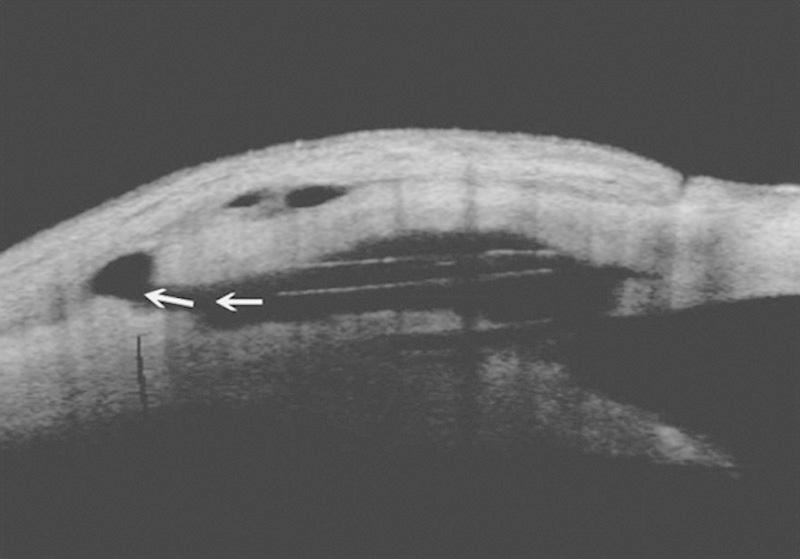

To report the safety and the effectiveness of deep sclerectomy (DS) with a new nonabsorbable uveoscleral hema implant (Esnoper-Clip) designed to increase trabecular and uveoscleral outflow and to achieve higher intrascleral blebs.

A significant decrease in intraocular pressure was observed after surgery, changing from a preoperative mean of 26.6±5.2 mm Hg to a postoperative mean of 15.3±5 mm Hg (P<0.001) at 12 months. There was also a significant reduction in the number of glaucoma drugs needed, varying from 2.5 per patient to 0.3 (P<0.001) 1 year after surgery. The main intrascleral lake height and volume at 12 months was 0.7±0.1 mm and 3.9±1.3 mm, respectively. No intraoperative complications occurred. The main postoperative complications were a positive Seidel test result at 24 hours in 2 eyes (7.4%), hyphema in 2 eyes (7.4%), and choroidal detachment in 1 eye (3.7%). All these complications resolved successfully. The need for additional mitomycin-C injections was recorded in 4 eyes (14.8%), twice in 2 of them. Twelve eyes (44.4%) underwent postsurgical Nd:YAG laser goniopuncture with a mean time between surgery and this procedure of 4.3 months. Mean intraocular pressure after Nd:YAG laser goniopuncture decreased from 19.2 to 15.5 mm Hg (P<0.001).

术后观察到眼压显著降低,12个月时从术前平均26.6±5.2 mmHg降至术后平均15.3±5 mmHg(P<0.001)。术后所需青光眼药物数量也显著减少,术后1年时从每位患者平均2.5种降至0.3种(P<0.001)。12个月时主要巩膜内湖高度和体积分别为0.7±0.1 mm和3.9±1.3 mm。术中无并发症发生。主要术后并发症为2只眼(7.4%)在24小时时Seidel试验结果为阳性,2只眼(7.4%)发生前房积血,1只眼(3.7%)发生脉络膜脱离。所有这些并发症均成功解决。4只眼(14.8%)记录有额外丝裂霉素C注射需求,其中2只眼注射了两次。12只眼(44.4%)术后接受了Nd:YAG激光房角穿刺,手术与该操作之间的平均时间为4.3个月。Nd:YAG激光房角穿刺术后平均眼压从19.2 mmHg降至15.5 mmHg(P<0.001)。

An ultrasound biomicroscopy study of filtering blebs after deep sclerectomy with a new acrylic implant.一项使用新型丙烯酸植入物进行深层巩膜切除术后滤过泡的超声生物显微镜研究。

Eur J Ophthalmol. 2011 Jul-Aug;21(4):391-9. doi: 10.5301/EJO.2010.5843.

Ultrasound biomicroscopy in deep sclerectomy.深层巩膜切除术中的超声生物显微镜检查

Eye (Lond). 2005 May;19(5):555-60. doi: 10.1038/sj.eye.6701558.

Ultrasound biomicroscopy images: long-term results after deep sclerectomy with collagen implant.超声生物显微镜图像:胶原植入物深层巩膜切除术后的长期结果

Graefes Arch Clin Exp Ophthalmol. 2002 Nov;240(11):918-23. doi: 10.1007/s00417-002-0567-7. Epub 2002 Oct 8.